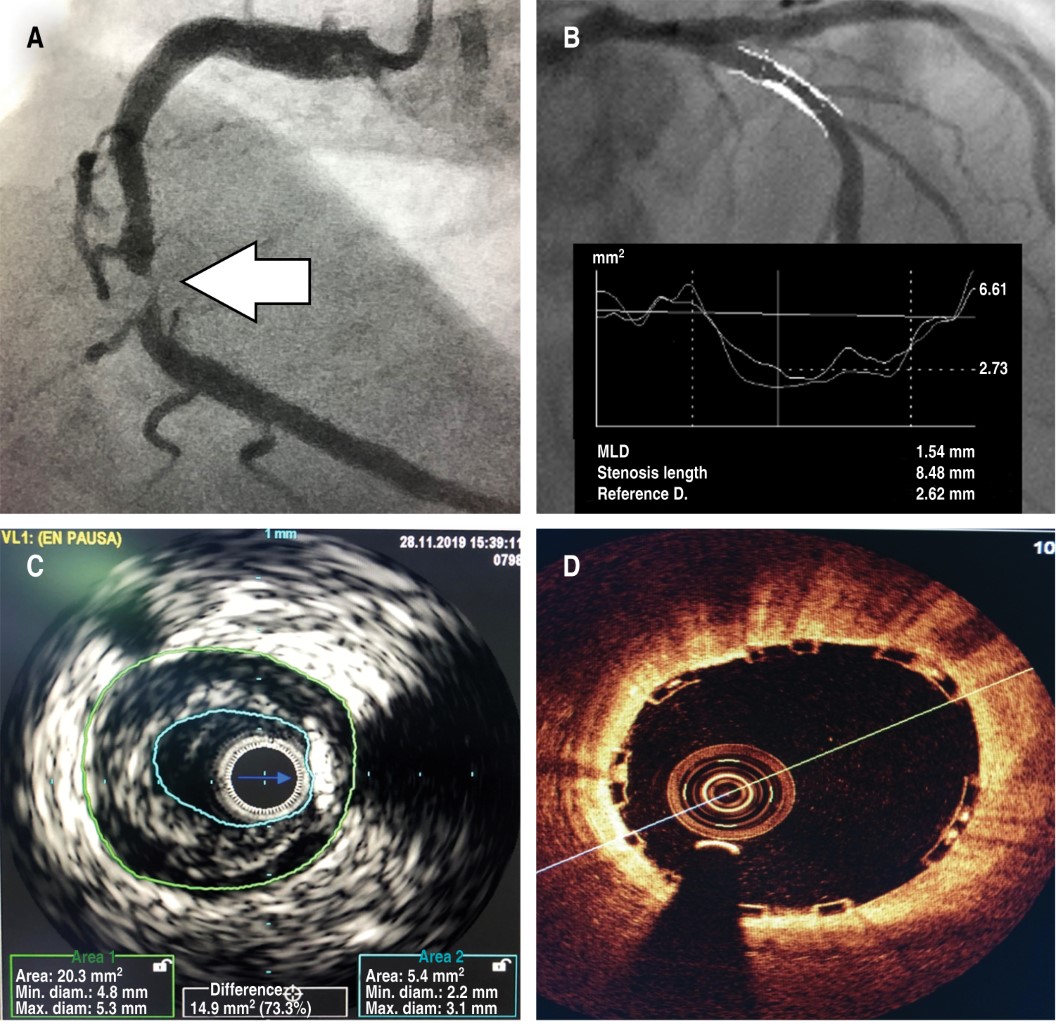

The images obtained of the coronary arteries by angiography only show the vascular lumen, seen in a two-plane projection. This allows the cardiologist to assess and measure the magnitude of the coronary lesions according to the degree of stenosis of the vascular lumen in relation to the "healthy" reference segments (Figure 1A).

Therefore, it is not possible to visualize the arterial wall, the degree of vascular remodeling, and the characteristics and volume of the plaque. Furthermore, it is necessary to obtain images in complementary projections to visually "reconstruct" the lesions when these are asymmetrical or eccentric. A stenosis is considered "significant" when it is > 50% of the visible diameter or if it obstructs > 75% of the vascular lumen area. Greater obstructions above these percentages have shown a reduction of the distal and reserve flow, as well as a high clinical correlation and with non-invasive ischemia stimulation studies.4 The direct subjective assessment of the occlusion magnitude will depend on the characteristics of the lesion, the quality of the radiographic images, angulation or the presence of secondary vessel branches or bifurcation. All this factors explain that a great intra and inter-observer variations could exist. The use of quantitative coronary angiography or coronary intravascular ultrasound may be necessary for a more precise characterization and evaluation of the plaque, especially in borderline, complex or difficult to assess lesions (Figure 1B). Even more, it would be ideal whenever possible, the use of functional tests such as the measurement of the pressure differences across a coronary artery stenosis through the "fractional flow reserve" (or FFR) with or without pharmacological therapy to evaluate the significance of the obstruction. This has proven not only to be a better form of identification of the repercussion of coronary stenosis, but also may establish therapeutic indication and prognosis in a more precise way. The cost and time of the procedure, however, has made its use infrequent in routine practice.

As mentioned, the main limitation of coronary angiography is that the images only depict the vascular lumen, creating a "luminogram". The IVUS permits the direct visualization from the interior of the vessel, enabling a circumferential analysis of the vascular wall. The procedure is done using a guiding catheter for coronary angioplasty and a 0.014" coronary guide wire. A special catheter containing the miniaturized ultrasound transducer of < 1 mm is then advanced to the distal segment of the coronary artery and a slow pullback is done, usually by a mechanical retraction system at a rate of 0.5 mm/s. The images obtained with transducers of 40 to 60 MHz, allow a full vision of the vascular wall at high resolution (Figure 1C). The procedure lasts an additional 10 to 15 minutes, and it may be performed as many times as necessary in a single intervention. The complications are quite uncommon with experienced hands, being coronary vasospasm the most frequent (1%). The information gathered represents a considerable segment of the entire length of the coronary vessel and it reveals the extension, magnitude, and characteristics of the disease with great detail, being important in the decision-making process. The measurement at the reference segments, and at the level of stenosis called "minimal luminal area" shows the severity of the lesion, being less than 4.0 mm2 a significant obstruction in non-left-main lesions. The length, volume, plaque characteristics, areas of dissection, vulnerable plaques or calcifications can be seen with great detail and may prove to be important in the decision-making process. In case of a percutaneous coronary intervention with a stent, it enables a better selection of the material and a better outcome through the optimal placement, attachment and post-dilation that decreases the complications of thrombosis and restenosis in the medium or long-term follow up. Undoubtedly, it is a great advance in the assessment of ischemic heart disease, and it let to make better therapeutic decisions.6

This novel imaging technique generates tomographic images from almost-infrared light produced by a rotational optic fiber. The images have a significantly higher resolution (10-20 µm) but less penetration. The technique to perform the procedure is similar to the one described for the intravascular ultrasound. The difference is that in order to avoid the interference of the red blood cells, it becomes necessary the administration of a contrast agent, synchronized with a rapid automated retraction system that obtains and reconstructs the images in seconds. It is ideal for visualizing the intimal layer, dissection areas and vulnerable plaques. The adequate placement and attachment of stents may be clearly seen even in longitudinal and even tridimensional reconstruction (Figure 1D). Although it is less used than IVUS, both techniques are useful and complementary.6